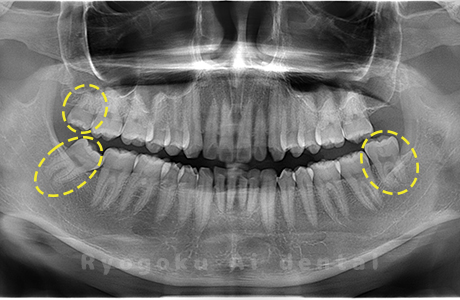

Case04

-

- 原因

- 上顎の親知らず、下顎の水平埋伏の親知らず

- 治療内容

- 上顎の親知らず、下顎の水平埋伏の親知らずを抜歯したケースです。

<リスク・副作用>

手術後は痛み、腫れ、痺れなどの副作用が生じる場合があります。